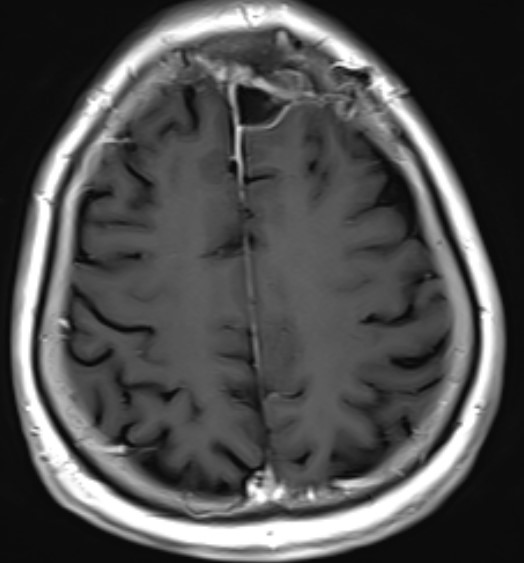

患者女性,62岁,因头晕一月在外院检查头部MR发现左额镰窦旁肿瘤来我院

完善术前检查在全麻下行左额开颅肿瘤切除术